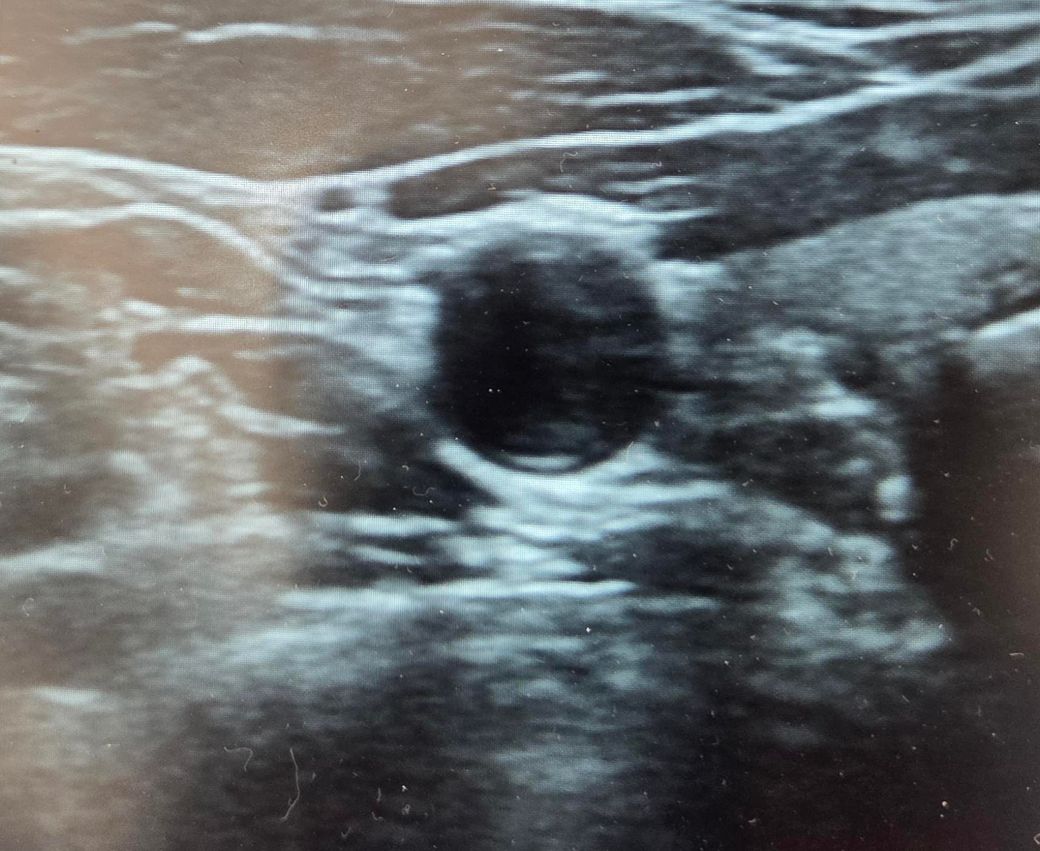

두번째 사진이 문제인데요.. 낭종이었는데 2년만에 석회화가 진행되었어요ㅜ 크기는 0.8센티로 변화는 없는데 세침해봐약겠죠?

• 1번 째 사진

갑상선 결절의 조직검사를 고려하는 경우는 갑상선 결절이 악성 즉 암인 가능성이 있는지에 따라

결정하게 됩니다. 초음파상 세로로 긴 모양,저음영,경계가 불규칙한 결절,미세석회화나 결절 주변부

석회화가 있는 경우는 악성 결절 가능성이 있어 생검을 고려할 수 있습니다. 좌측 사진은 단순 낭종으로

보이지만 우측 사진은 고형성분이 포함되어 있는 결절이며 주변부 석회화가 있어 생검을 고려해야 합니다.

따라서 세침 흡인 검사가 가능한 병원 내원하여 검사를 하는 것을 권해드립니다.